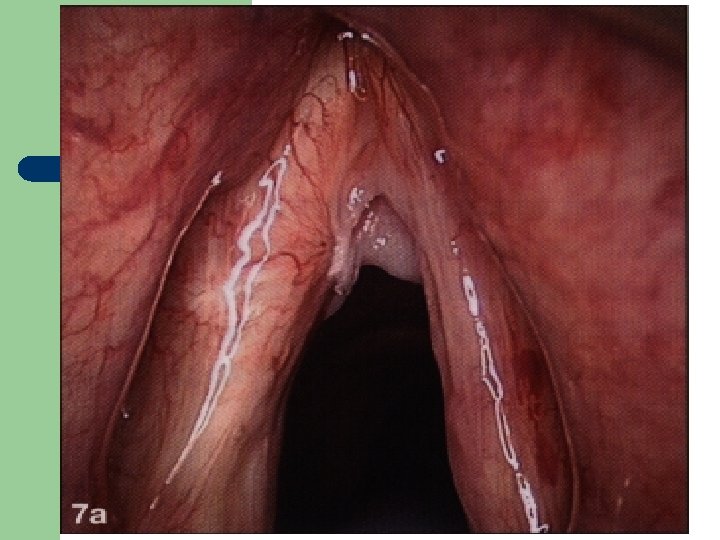

Hlasivkový uzlík l

Hlasivkový uzlík l

Hlasivkové uzlíky l